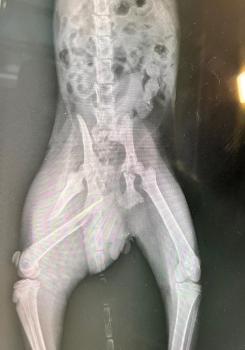

Er humpelte und litt starke Schmerzen. Beim Tierarzt stellte sich heraus, dass sein Oberschenkelknochen gebrochen war. Er wurde erfolgreich operiert und hat nun eine Platte im Bein, so dass der Knochen in der richtigen Position heilen kann. Dazu ist auch strenge Käfigruhe angesagt.